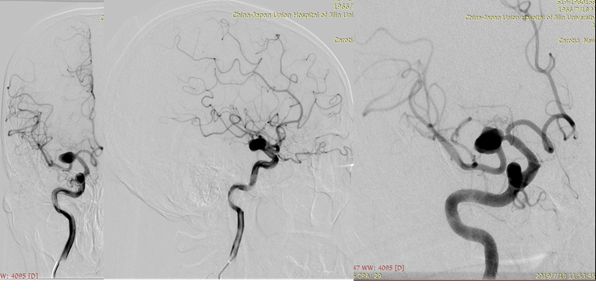

术前造影:

2、术后18小时急诊DSA(图六)。

图六

DSA术前后对比(图七)。

图七